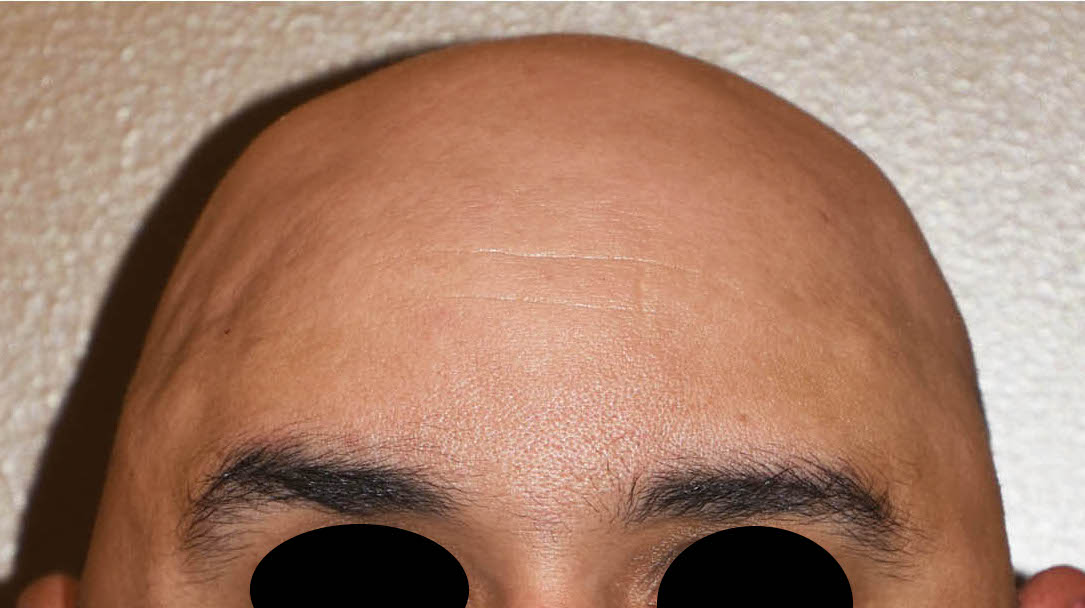

Patient 100

Desire for reshaping of an asymmetric flat back of the head in a shaved head male.

A combined back of the head reshaping procedure was done with a custom skull implant, sagittal ridge reduction and a right temporal muscle reduction.